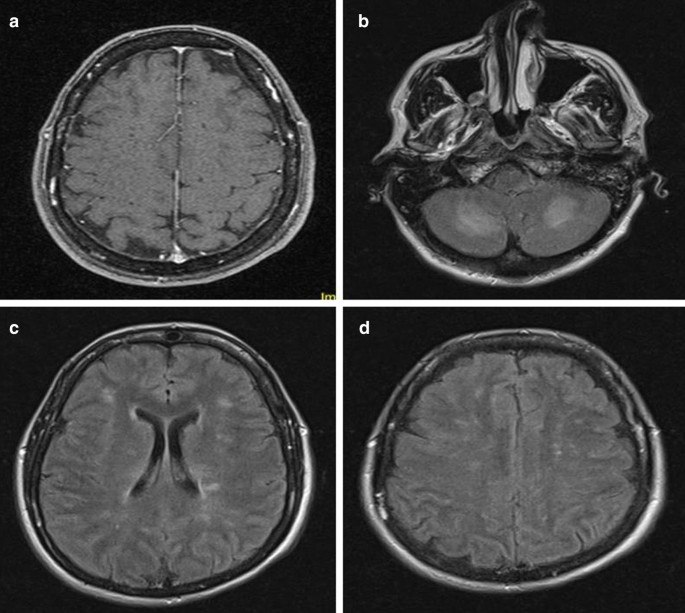

After 24 hours of therapy, the patient showed an improvement in blood chemistry (CPR 8.3 mg/dl; PCT 7.7 ng/ml; lactate 4.1 nmol/l) and hemodynamic parameters (CO 3.2 l/minute; SVR 550 dyne seconds/cm5, MAP 70 mmHg). Her body temperature was 36.5 °C. GCS score remained 5 (E1, V1T, M3) when another sedation window was performed. Her hemodynamic stability allowed her to undergo a brain magnetic resonance imaging (MRI) scan (Fig. 1). The MRI scan revealed an altered signal and post-contrast enhancement of the leptomeninges. Moreover, multiple T2 and fluid-attenuated inversion recovery (FLAIR) hyperintense and sometimes confluent lesions were detected: in the thalamus, which appeared swollen; in the pons, in the cerebellar peduncles, and in cerebellar hemispheres, also appearing swollen; in the ventricles (mostly in the lateral ventricles and in the occipital horn bilaterally); and in the parahippocampal region bilaterally. All these lesions were also characterized by a reduced diffusivity in diffusion-weighted imaging (DWI) scans.

Images from the first MRI scan. a T1-weighted image showing meningeal post-contrast enhancement. b FLAIR image demonstrating bilateral cerebellar hyperintense lesions in both hemispheres. c FLAIR image showing periventricular hyperintensity and multiple white-matter hyperintense lesions. d FLAIR image demonstrating multiple juxtacortical white-matter lesions

Finally, multiple comminute T2/FLAIR white-matter hyperintense lesions were demonstrated, located in the juxtacortical white matter, especially in frontal regions, in both the corona radiata, and in periventricular regions bilaterally.

MRI examination is another peculiar issue of our case that is worth highlighting. MRI allows the detection of subtle changes in brain and meningeal parenchyma, helps in differential diagnosis, and is a useful tool to monitor complications, treatment response, and disease evolution [34,35,36,37,38]. Meningitis may be accompanied by several other alterations that are reported in a considerable number of patients: ventricular involvement, with ependymal enhancement in T1 scans, hyperintense images in T2/FLAIR imaging, and reduced diffusivity in DWI; hydrocephalus; cerebral edema; cerebritis with T2/FLAIR hyperintense lesions and a reduction of diffusion in DWI, mostly involving cortical regions and juxtacortical white matter; vascular congestion, venous thrombosis, and ischemic lesions; and subdural empyema and cerebral abscesses [34,35,36,37,38]. Our patient did display some of these alterations, such as leptomeningeal enhancement, ventricular/ependymal involvement, multiple T2/FLAIR hyperintense lesions, and multiple areas of diffusivity reduction in DWI scans. Of note, she had dramatic cerebellar involvement; cerebellitis is a rare condition in adult patients, being more common in pediatric populations [39, 40]. Moreover, although bacterial etiology is seldom reported, cerebellar inflammation is more often caused by viral infection or postinfection and autoimmune conditions [39, 40]. Although a full recovery is infrequently described in adult patients [39], she exhibited a brilliant recovery from her cerebellar symptoms in only a few weeks.